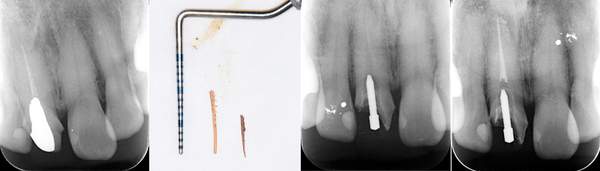

根の先端に膿が溜まっています。

根の中の白い縦の線がなくなっています。これは、中に詰まっていた、防腐剤を取り除いた証拠になります。取り除いてから、根の中をしっかり清掃していきます。

清掃が終わり、患者様も違和感がなくなったということで、防腐剤を再び詰めていきました。最初に入っていたものと比較して緊密に太く入っているのがわかります。

6ヶ月後。根の先端に溜まっていた膿(黒い影)がなくなっています。なくなったことが確認できてから、かぶせ物をかぶせていきます。

根の中に入っていた防腐剤を取り除いた時の写真です。感染物質が付着して黒くなっているのがわかります。

また、防腐剤をとりのぞけても、その防腐剤を歯の根のなかにくっつける素材が残っていますので、それもしっかり取り除きます。

目ではなかなか全てを見ることができないので、右の写真の様にマイクロスコープをもちいて拡大してみていきます。

こちらは根の途中までしか防腐剤がはいってませんでした。患者様が違和感を訴えたため、治療を行いました。防腐剤を取り除き、根の中を清掃し、根の先端までしっかり防腐剤をいれました。